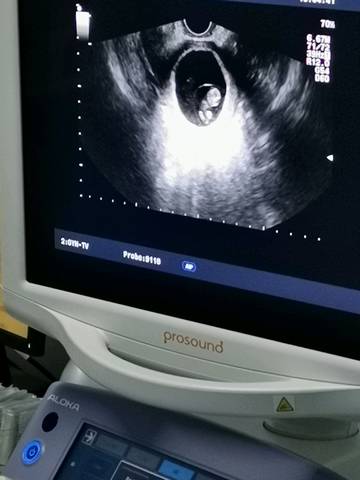

好神奇,突然流血去医院检查你还在!我的玻璃心

出的多吗?我五周多点,估计提了重物,刚出了点血,吓死我了